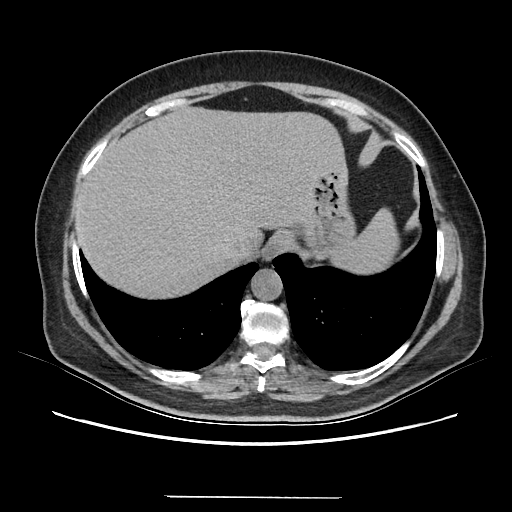

Original NATIVE CT scan (input)

Full window (WL 1023.5, WW 4095 β†’ Low βˆ’1024, High +3071)

Actual HU range: [-160.0, 240.0]